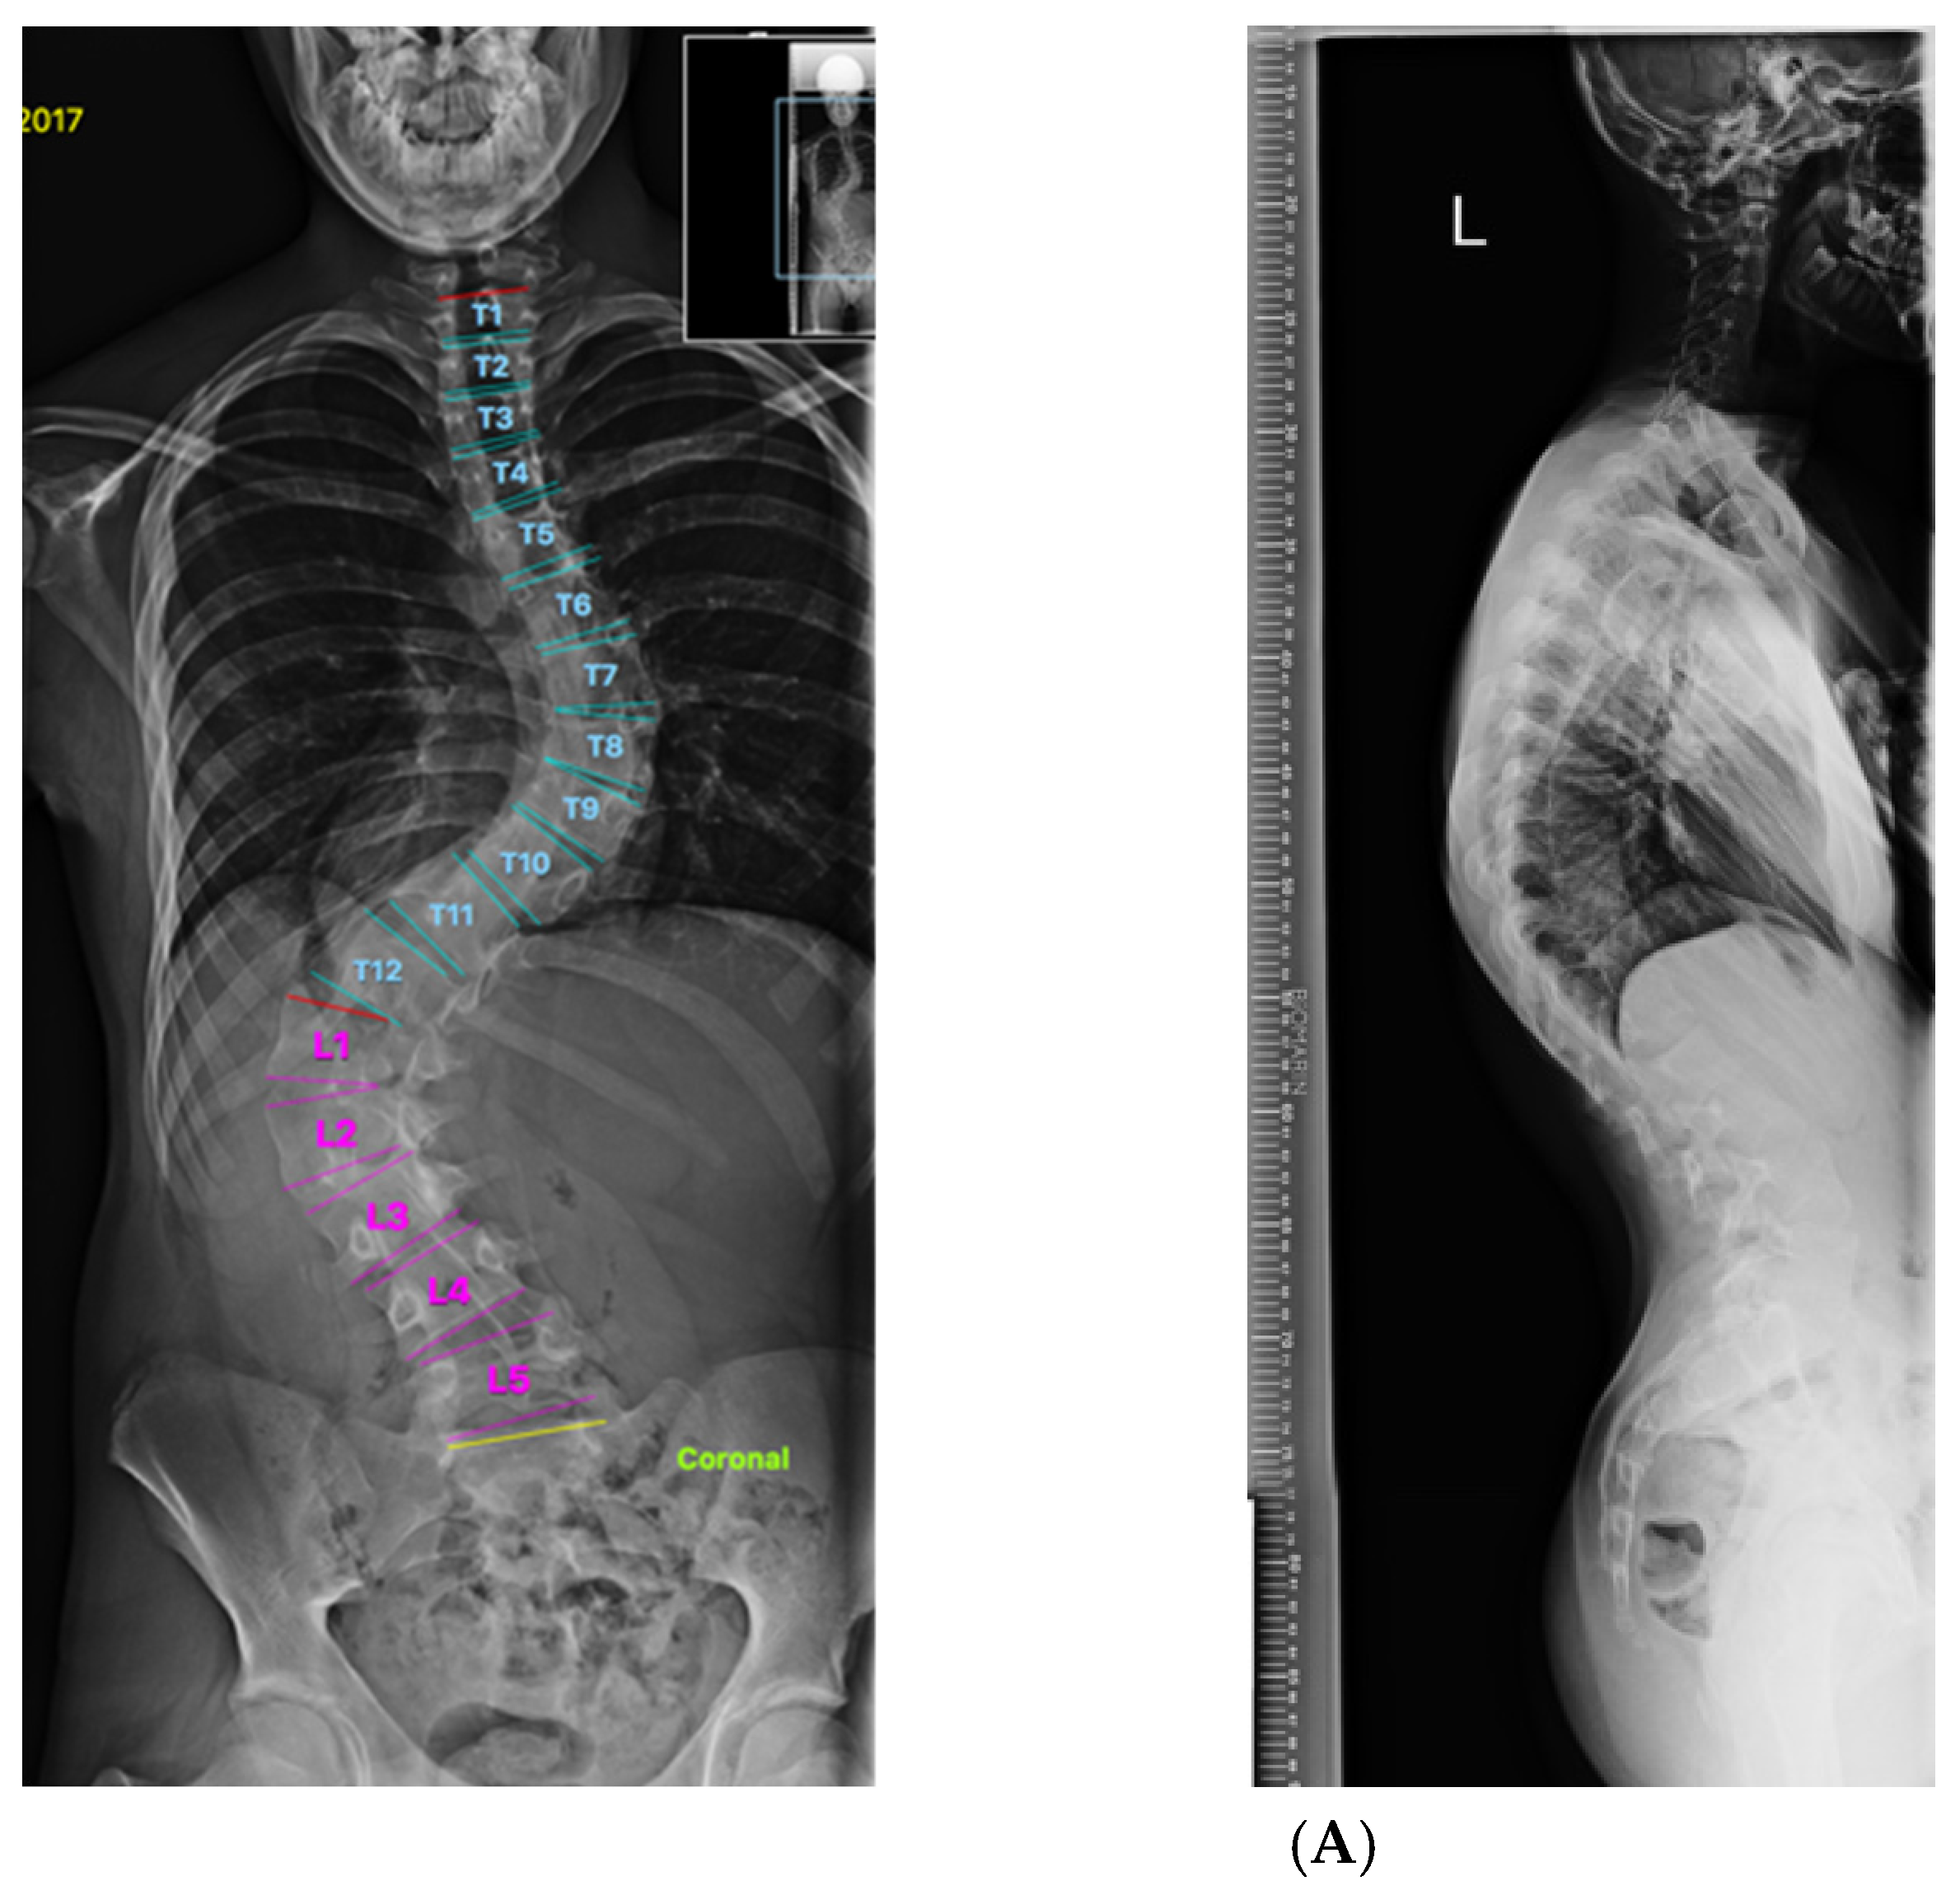

2. Materials and Methods